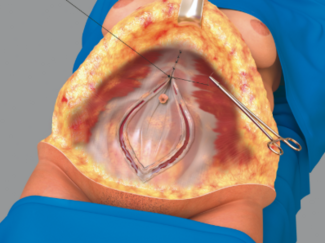

Michael Rice, FRCS; Giulia Colavitti, FRCS; Philippa Jackson, FRCS; Sherif Wilson, FRCS

This novel technique for nipple areolar complex reconstruction is supported by a systematic review of the current literature.